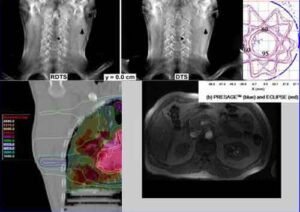

E' un'innovativa tecnica di chirurgia oncologica radioguidata, che utilizza al posto della radiazione gamma, cioe' i fotoni oggi comunemente impiegati,...